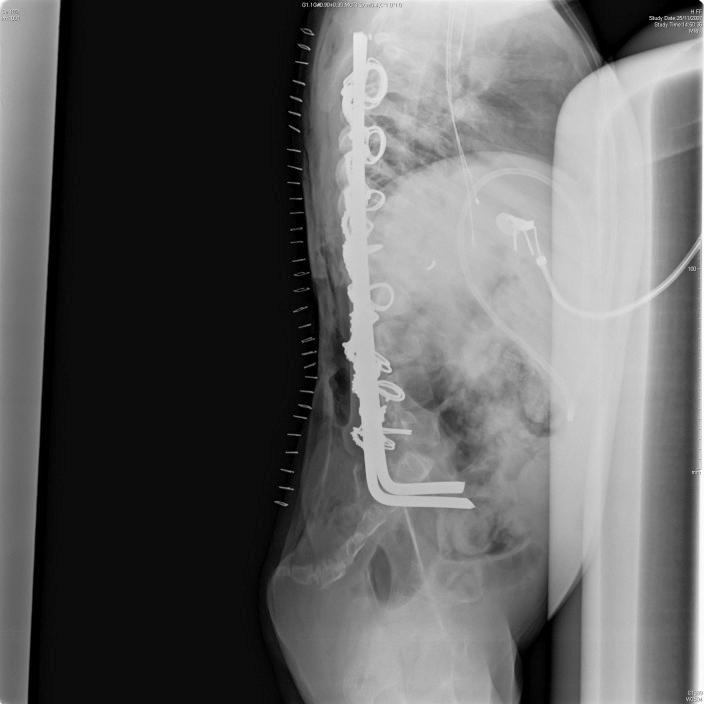

采用节段性脊柱骨盆固定术对脊髓脊膜膨出(MMC)患者先天性脊柱后凸进行手术矫正的长期疗效。

Long-term outcome of surgical correction of congenital kyphosis in patients with myelomeningocele (MMC) with segmental spino-pelvic fixation.

A retrospective case series of patients with myelomeningocele (MMC) who underwent kyphectomy and posterior segmental fixation using Luque rods and 16-gauge wires.

Thirteen consecutive patients who underwent posterior kyphectomy for transforaminal fixation contiguous to "everted lamina." Fusion rates, time to fusion, change in Cobb angle, complications, and improvement in activities of daily living using the Katz score were measured.

Average age at time of surgery was 9.2 (range, 4.5-17) years. Average time to follow-up was 120 (range, 20-310) months. Solid fusion was achieved in 9 patients (69%) with a mean time to fusion of 12 months. The mean postoperative kyphotic curve was 22° with an average correction of 90°. Five patients (38%) experienced a postoperative complication. The mean improvement in activities of daily living score was 1.6 points and all patients achieved independent sitting balance.

Segmental spino-pelvic fixation is a solid alternative mode of fixation in patients with MMC with congenital kyphosis. Patient selection, proper perioperative multidisciplinary assessment, and surgeons' expertise are significant in the success of this complex surgery.METHODS evaluation and class of evidence (CoE)STUDY DESIGN: Prospective cohort Retrospective cohort Case control Case series•METHODS Patients at similar point in course of treatment• Follow-up ≥ 85%• Similarity of treatment protocols for patient groups• Patients followed-up long enough for outcomes to occur Control for extraneous risk factorsOverall class of evidenceIVThe definiton of the different classes of evidence is available on page 63.

对一系列接受了驼背矫正术以及使用鲁克棒和16号钢丝进行后路节段固定的脊髓脊膜膨出(MMC)患者进行回顾性病例分析。

连续纳入13例接受后路驼背矫正术以进行与“翻转椎板”相邻的经椎间孔固定的患者。测量融合率、融合时间、Cobb角变化、并发症以及使用Katz评分评估的日常生活活动改善情况。

手术时的平均年龄为9.2岁(范围4.5 - 17岁)。平均随访时间为120个月(范围20 - 310个月)。9例患者(69%)实现了牢固融合,平均融合时间为12个月。术后平均后凸曲线为22°,平均矫正度为90°。5例患者(38%)出现术后并发症。日常生活活动评分的平均改善为1.6分,所有患者均实现了独立坐位平衡。

节段性脊柱骨盆固定是治疗先天性脊柱后凸的脊髓脊膜膨出患者的一种可靠固定方式。患者选择、适当的围手术期多学科评估以及外科医生的专业技能对这项复杂手术的成功至关重要。方法评估和证据等级(CoE)